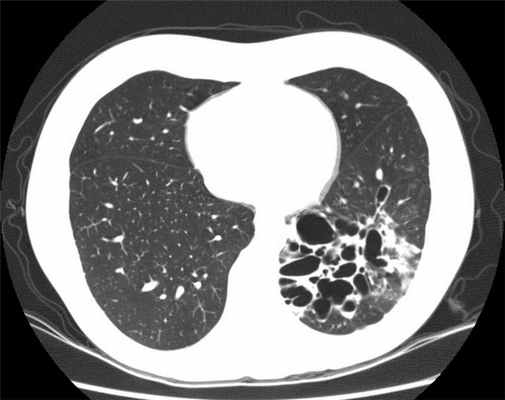

- КТ (компьютерная томография): это исследование необходимо для диагностики бронхоэктазов. При этом ваше тело подвергается рентгеновскому облучению под разными углами с последующим компьютерным составлением изображения с высокой точностью.

В окончательной постановке диагноза важнейшее значение имеют лучевые методы диагностики. При рентгенографии выявляются тяжистость, ячеистость, кистовидные изменения лёгочного рисунка, уменьшение объёмов отдельных зон лёгкого, эмфизематозность (воздушность) в смежных участках лёгкого. В настоящее время основным диагностическим исследованием является компьютерная томография (КТ, МСКТ). Это связано с большой информативностью метода при неинвазивном и безопасном характере его применения.

Диагностика бронхоэктатической болезни

Исследование, позволяющее получить данные о состоянии органов грудной клетки и средостения.